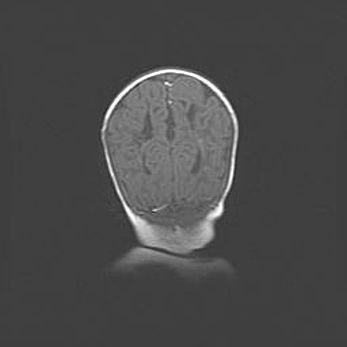

Сообщающаяся гидроцефалия. Кистозная энцефаломаляция головного мозга.

Возраст: 3 месяца 4 дня

Вес: 3100 г

Пол: женский

Окружность головы: 34 см

Срок гестации: 31 неделя

Кистозная энцефаломаляция головного мозга - одна из форм поражения головного мозга в детском возрасте. Характеризуется возникновением множественных и распространённых кист в коре, белом веществе и подкорковых образованиях головного мозга у плодов, новорождённых и детей раннего возраста. Развитие кистозной энцефаломаляции связано с внутриутробной асфиксией и гипотонией, родовой травмой, тромбозом синусов, пороками развития сосудов, инфекциями, сепсисом и другими причинами. Наиболее значимые инфекционные агенты: вирусы простого герпеса, цитомегалии, краснухи, токсоплазмы, энтеробактерии, золотистый стафилококк и другие.